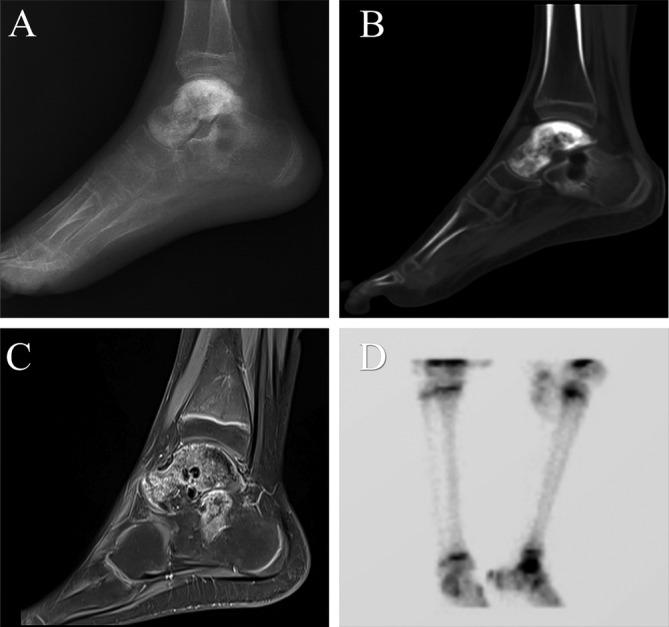

Here, we present the case of an 11-year-old adolescent patient diagnosed with Ewing's sarcoma of the talus, accompanied by suspected involvement of the calcaneus. Following a comprehensive evaluation, a 3D-printed talus-calcaneus prosthesis, which is composed of a ultrahigh-molecular weight polyethylene (UHMWPE) part and a titanium alloy part, was designed for talus and calcaneus reconstruction. In addition, a porous structure was designed to promote the integration of bone-prosthesis interface. The lesion was completely resected and the prosthesis was precisely installed. After 12 months follow-up, patients demonstrated favorable function results with the Musculoskeletal Tumor Society (MSTS) score was 27/30, and the American Orthopedic Foot and Ankle Society (AOFAS) score was 92/100. The range of motion for dorsiflexion, plantarflexion, inversion, and eversion of the right ankle joint was measured as 10° and 35°, 15°, and 10°, respectively. The postoperative radiograph showed a good position of the prosthesis. No narrowed joint space was observed. Tomosynthesis shimadzu metal artifact reduction technology (T-SMART) revealed that integration between bone and prosthesis was good.